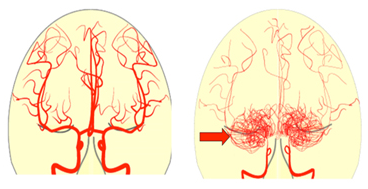

모야모야병(Moyamoya Disease)은 뇌의 주요 혈관인 내경동맥이 점차 좁아지거나 막혀, 뇌로 가는 혈류가 줄어들고, 이를 보상하기 위해 뇌 안에 가느다란 새로운 혈관이 형성되는 희귀 질환입니다. 이 혈관들은 뇌혈관조영술 영상에서 연기처럼 퍼지는 모습으로 보이는데, 일본어로 ‘모야모야’(もやもや)는 안개가 자욱한 모양을 의미합니다. 이러한 특이한 혈관 소견 때문에 ‘모야모야병’이라는 명칭이 붙었습니다. 주로 "소아기와 청장년기(20~40대)"에 발생하며, 뇌출혈, 뇌경색, 일과성 허혈 발작 등을 유발할 수 있어 조기 발견과 치료가 매우 중요합니다.

- 뇌혈관의 좁아진 부위 및 대체 혈관망(모야모야 혈관)을 시각화함

- 모야모야 혈관의 특성적인 모습(연기처럼 퍼짐)을 확인할 수 있음